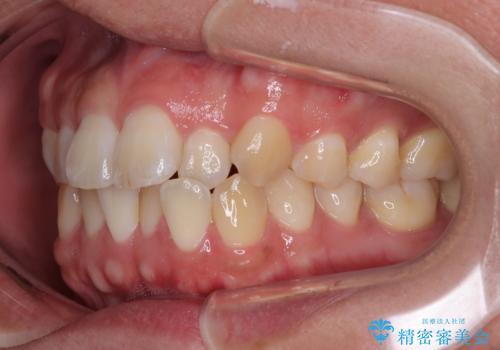

- 前歯の反対咬合などを気にして来院された患者様です。

ワイヤー矯正、マウスピース矯正どちらでも対応可能であったので、ご本人の希望によりインビザラインにて矯正治療を行うこととしました。

毎日の装着時間をしっかりと守ってくださり、1年強の短期間で、あっという間に治療を終えることができました。